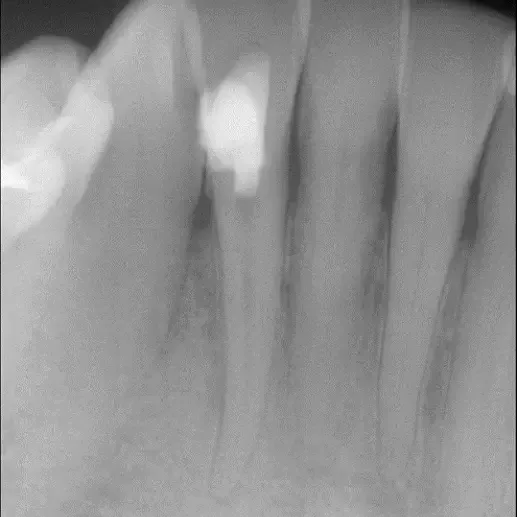

Fall 1: Revisionsbehandlung

Kontrolle nach Wurzelfüllung